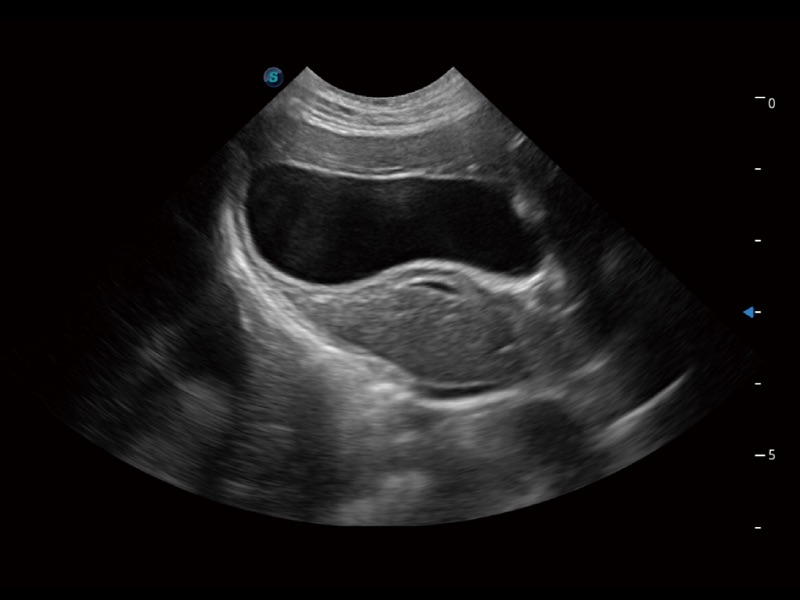

一键自动识别膀胱壁及自动测量膀胱容积,不受膀胱形状和大小的限制,帮助医生快速精准获得测量的数据。

ProPet 70 进一步提升了微米成像算法,更加注重对基础原始图像的还原和保留,在有效减少斑点噪声、增强组织边界显示的同时,避免过度优化丟失真实的解剖信息。